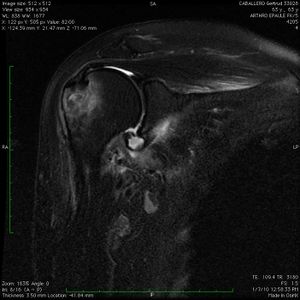

Magnetic Resonance Arthrogram (MRA)

Contrast enhancement during magnetic resonance arthrogram (MRA) is of great value and will increase the sensitivity of magnetic resonance imaging (MRI) in identifying a soft tissue injury (cartilage, rotator cuff, labral tears (Figure), a patulous capsule (Figure), reverse humeral avulsion of the glenohumeral ligaments (rHAGL, Figure), associated findings such as paralabral cysts) (Figure).